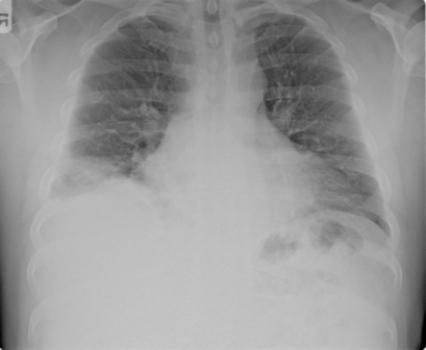

This portable AP chest radiograph shows a patient with: